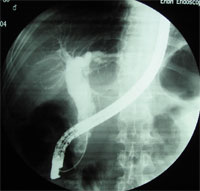

1.膽管造影多採用PTC術,具有診斷和治療的雙重作用。可以發現擴張的膽管和梗阻的部位、原因,但嚴重休克病人一般不宜立即作此項檢查。

2.CT和MRI檢查當高度懷疑肝內外膽管梗阻而B超檢查未能確立診斷時,可行CT或MRI檢查。CT或MRI對於明確梗阻部位、引起梗阻的原因明顯優於B超檢查,其準確率可達90%以上。

3.超音波檢查B超檢查已成為首選的檢查方法。探查膽囊結石、膽總管結石及肝內膽管結石的診斷符合率分別為90%、70%~80%和80%~90%。可發現結石阻塞部位的膽管和(或)肝內膽管擴張,並可了解膽囊的大小、肝臟大小和有無肝膿腫形成等。